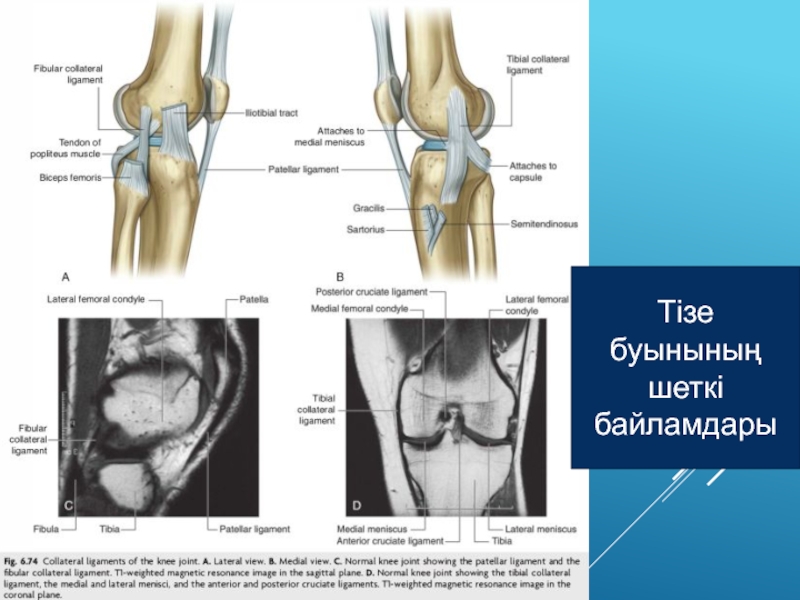

Слайд 39Тізе буынының шеткі байламдары

Слайд 40Тізе буының артқы байламдары